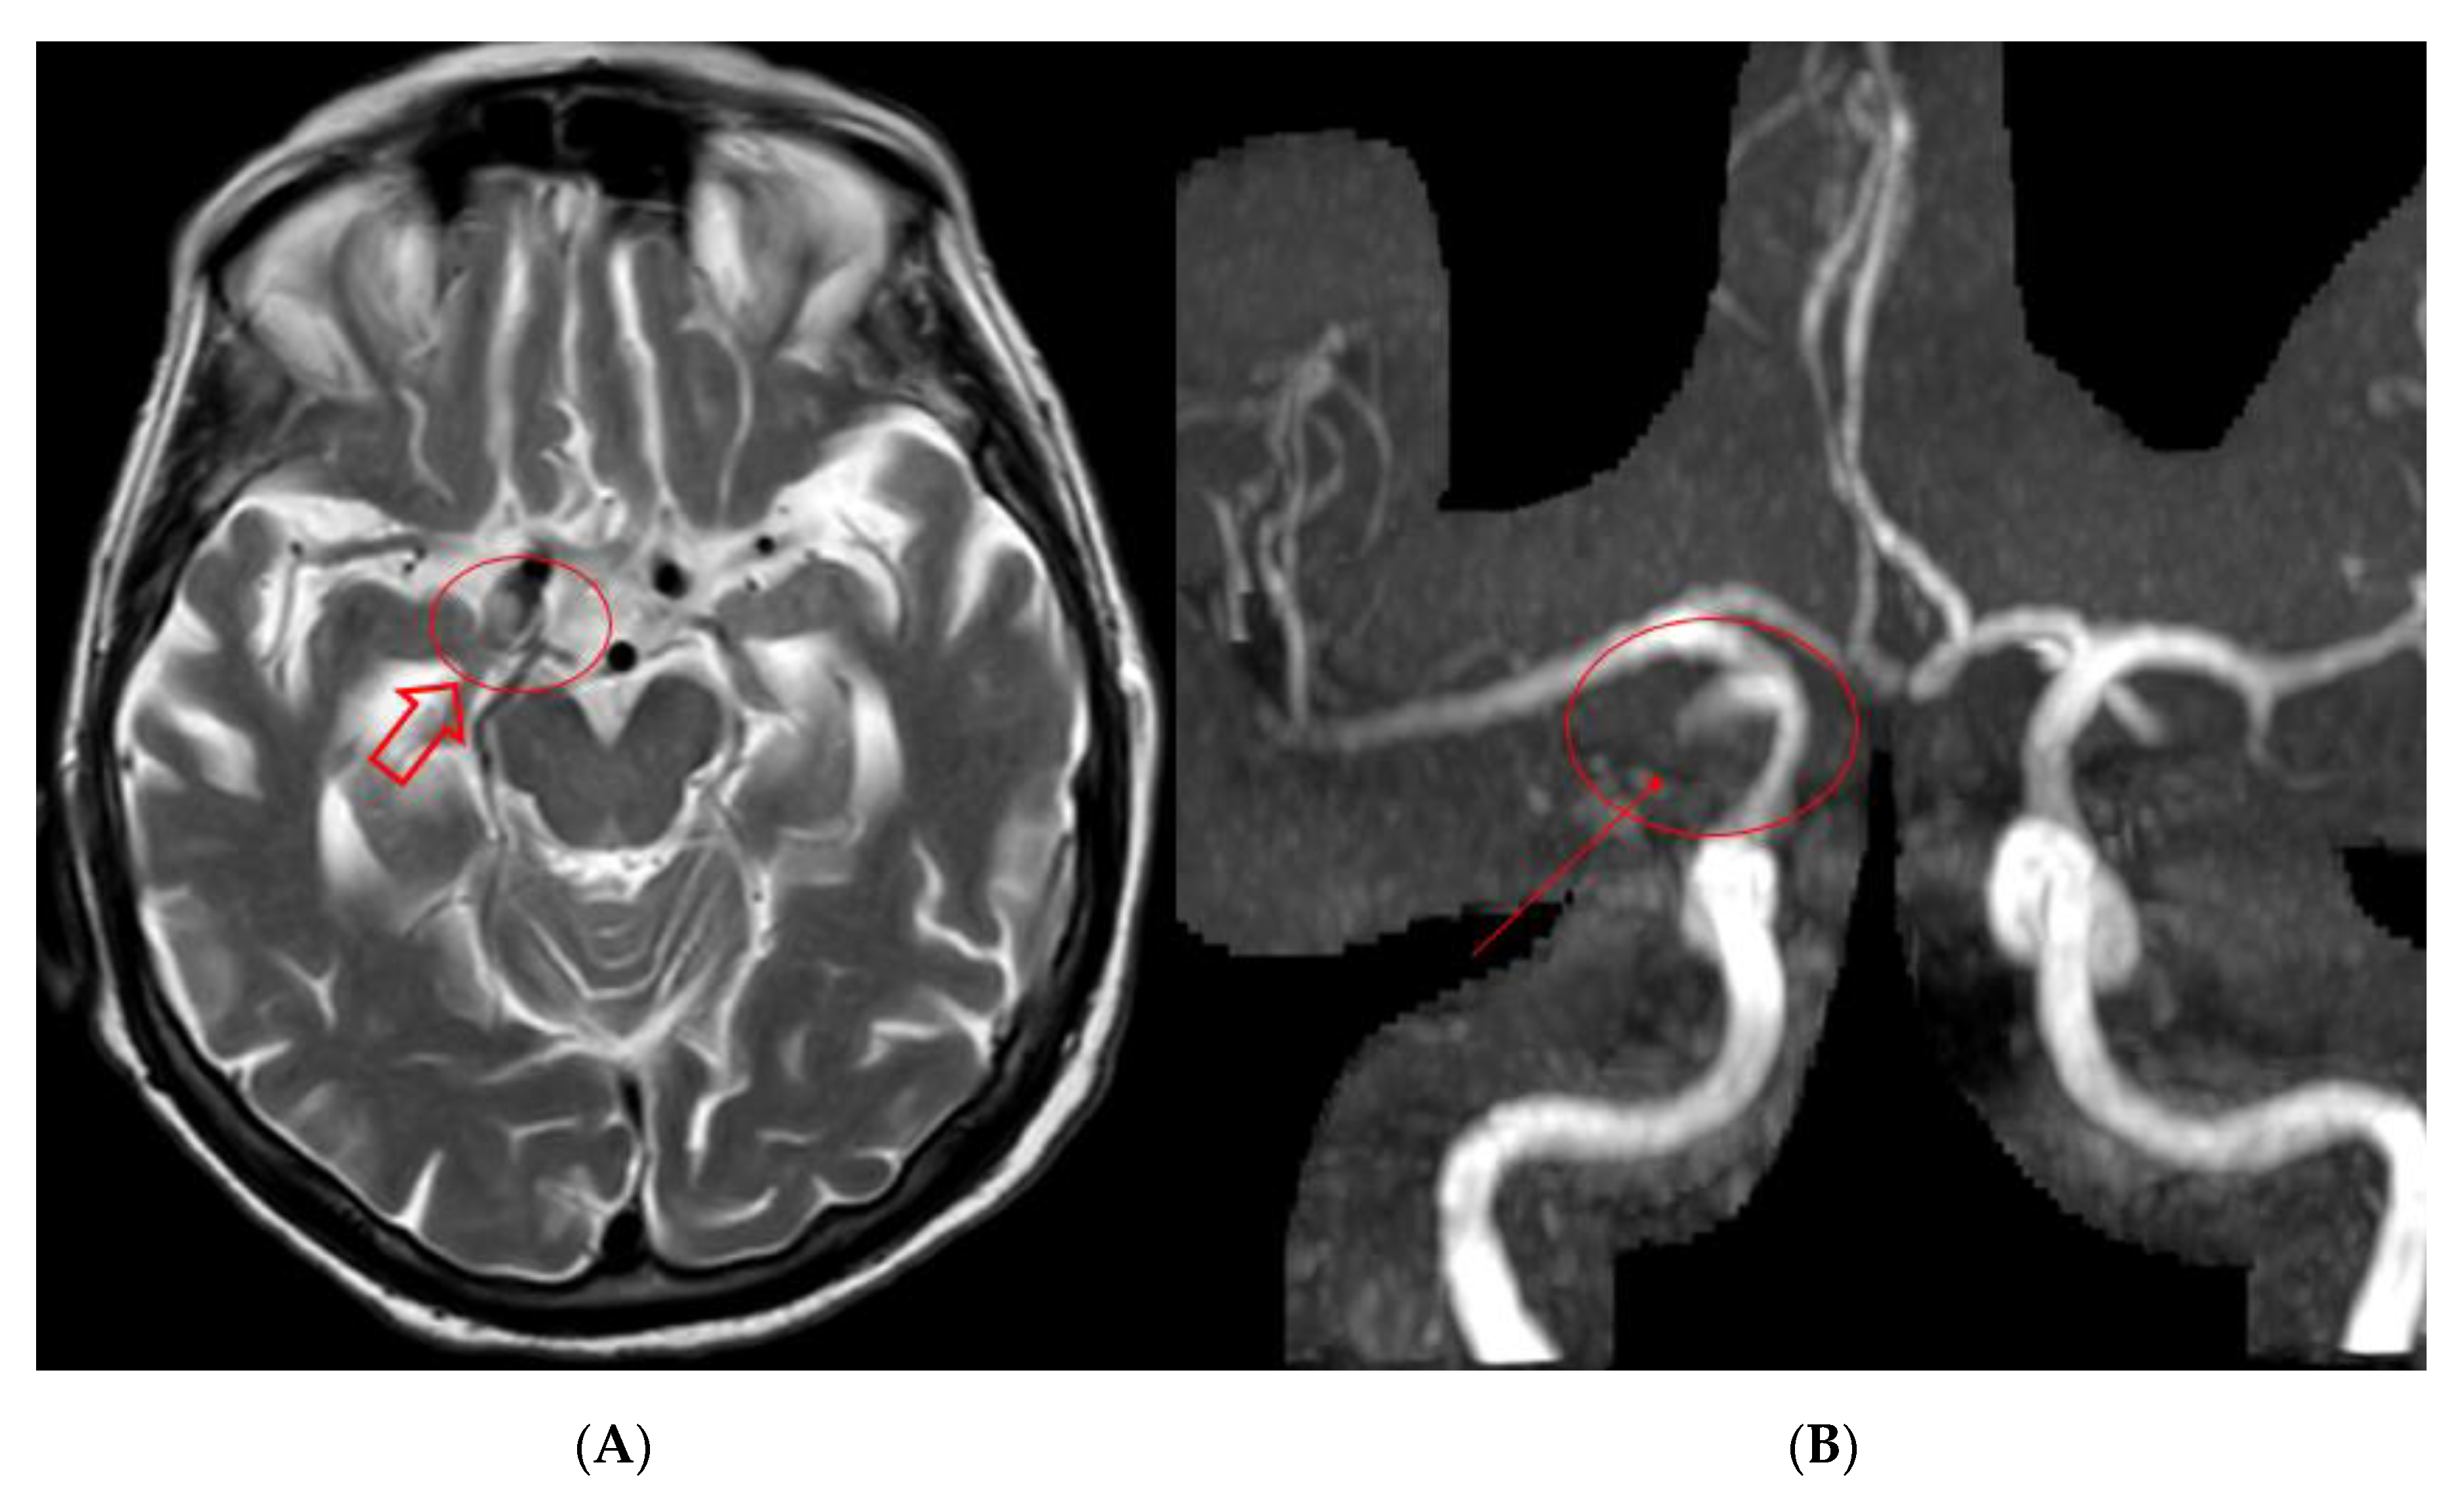

2. Case Presentation